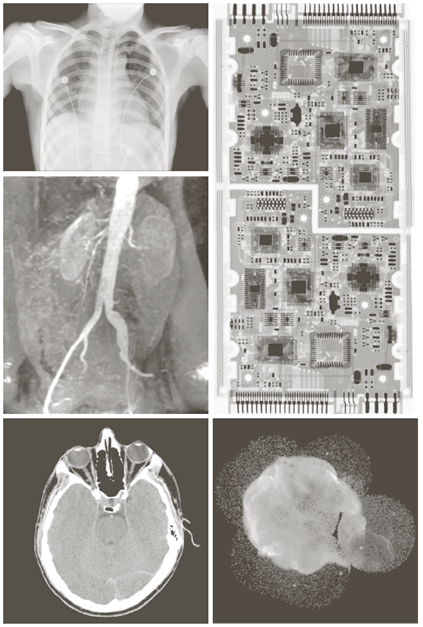

X-ray image

a) 항암제 Taxol b) 콜레스테롤 c) 마이크로프로세서

Visual band image – 영상처리에 의한 품질검사

a) 회로 기판

b) 포장 알약